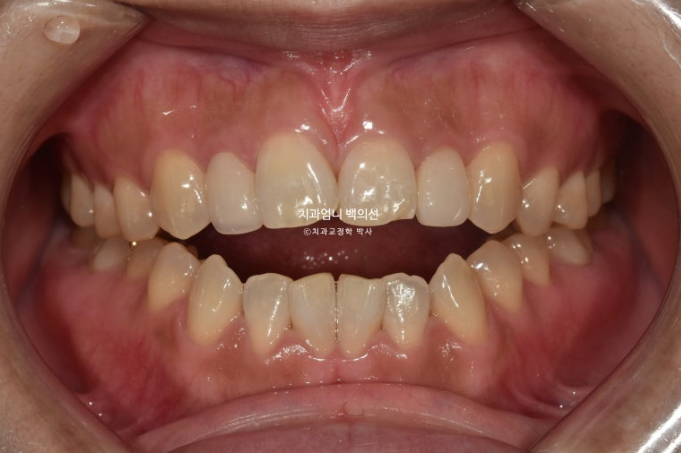

2년전 앞니 개방교합 치료를 위해 내원한 30대 환자분입니다.

앞니 벌어진 양이 5mm라 양악수술과의 경계지만 양악수술생각은 없으셔서 교정만으로 해결하기로 했습니다.

앞니 약간 삐뚠 부분도 함께 해결하기로 하고 치료에 들어갑니다. 클리피씨 교정을 권유드렸습니다.